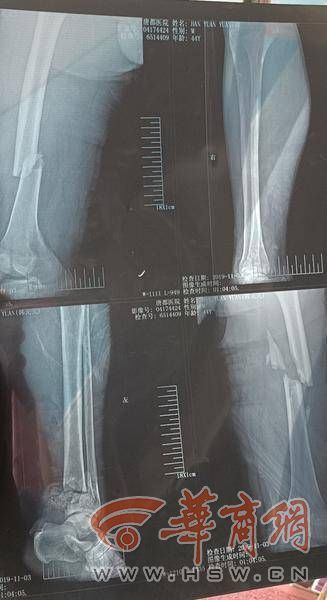

医院诊断证明显示,韩师傅左胫腓骨远端开放性骨折,双侧股骨中段开放性骨折,左侧股骨颈基底部骨折,左侧第5肋骨骨折,右锁骨骨折,左下肢皮肤缺损,右小腿肌间静脉血栓形成。

去年12月10日经司法鉴定,韩师傅因交通事故致全身多发性骨折,经积极治疗损伤基本愈合,但因左胫腓骨远端开放粉碎性骨折,目前仍断端移位,踝关节结构严重破坏,导致踝关节活动严重受限,其功能损失达75%以上,此损伤程度已构成重伤二级。双侧股骨干中段粉碎性骨折,经积极治疗,目前愈后尚可,此损伤程度属轻伤一级。右侧锁骨骨折,此损伤程度属轻伤二级。最终给出的鉴定意见为:被鉴定人损伤程度属重伤二级。